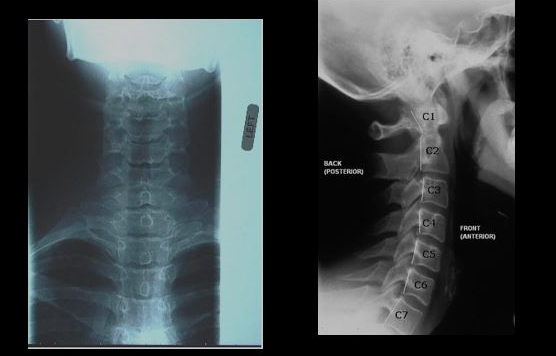

목디스크 치료방법을 알아보기 전에 발생할 수 있는 3가지 유형의 목 디스크 문제를 이해하는 것이 중요합니다. 목디스크는 다음과 같이 분류가 됩니다.

1.1 경추 디스크 변성

경추의 디스크가 유연성, 탄성 및 충격 흡수 특성을 잃기 때문에 나이가 들면서 발생하는 자연스러운 과정입니다.

1.2 경추 추간판 탈출증

이 상태는 디스크의 내부 젤 같은 핵이 외부 섬유층의 찢어진 틈을 통해 돌출되어 잠재적으로 신경을 압박하고 통증이나 신경학적 증상을 유발할 때 발생합니다.

1.3 경추 추간판 벌지 (Bulge)

추간판 벌지 (부풀어 오른 디스크)는 덜 심각한 형태의 추간판 탈출증으로, 추간판의 바깥층이 정상적인 경계를 넘어 확장되지만 파열되지는 않습니다.